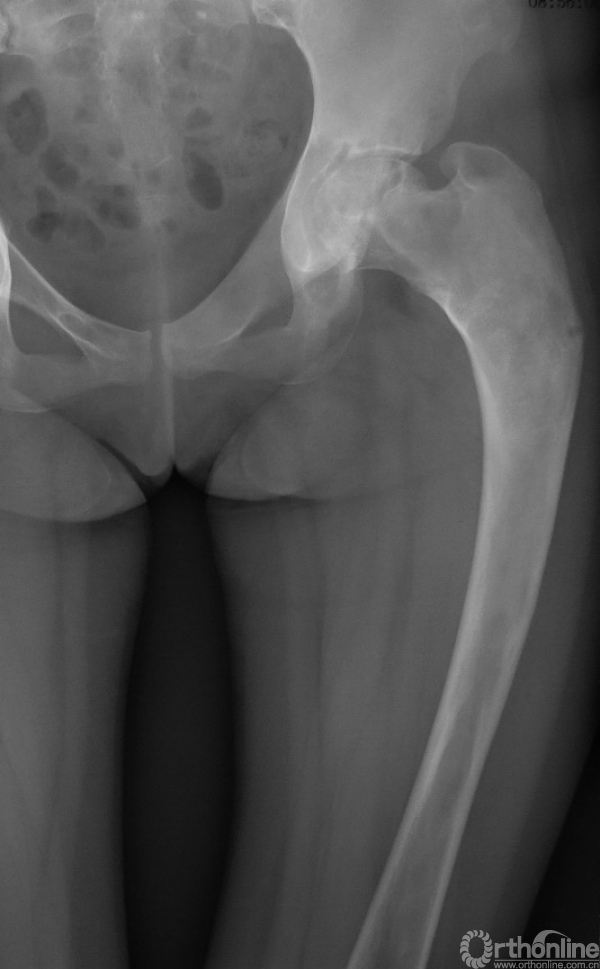

本病女性多见,男女发病率约为1.2:3,多在10岁左右发病,主要症状为轻微疼痛,局部肿胀及压痛。因症状轻微往往被忽略,多数病例是在以后查体或发生病理骨折时才被发现,骨折时疼痛可突然加重,肢体功能障碍,但骨折很少移位(图1),由于受累骨的坚固性受到明显影响,肢体可出现弯曲畸形,发生于股骨近端的常形成髋内翻,被称为“牧羊拐畸形”(图2)。

图1 股骨病理性骨折,没有明显的移位